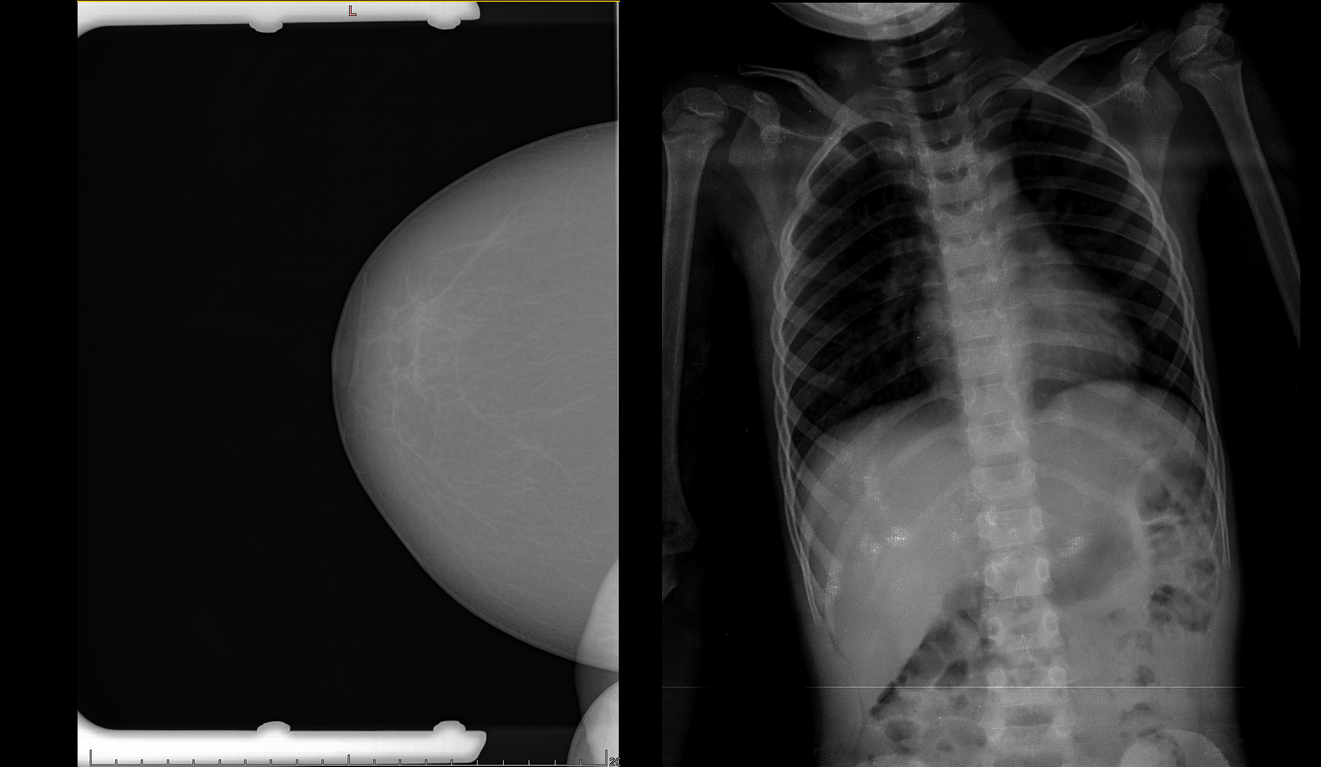

В ходе усиленного мониторинга после подключения новых клиентов часто выявляются всякие нестандартные кейсы, которые нужно разбирать отдельно.

Слева - на исследовании видны рамки, которые в некоторых случаях ещё и залезают на область молочной железы. Справа - рентген ребёнка, на которых наша система работать не предназначена